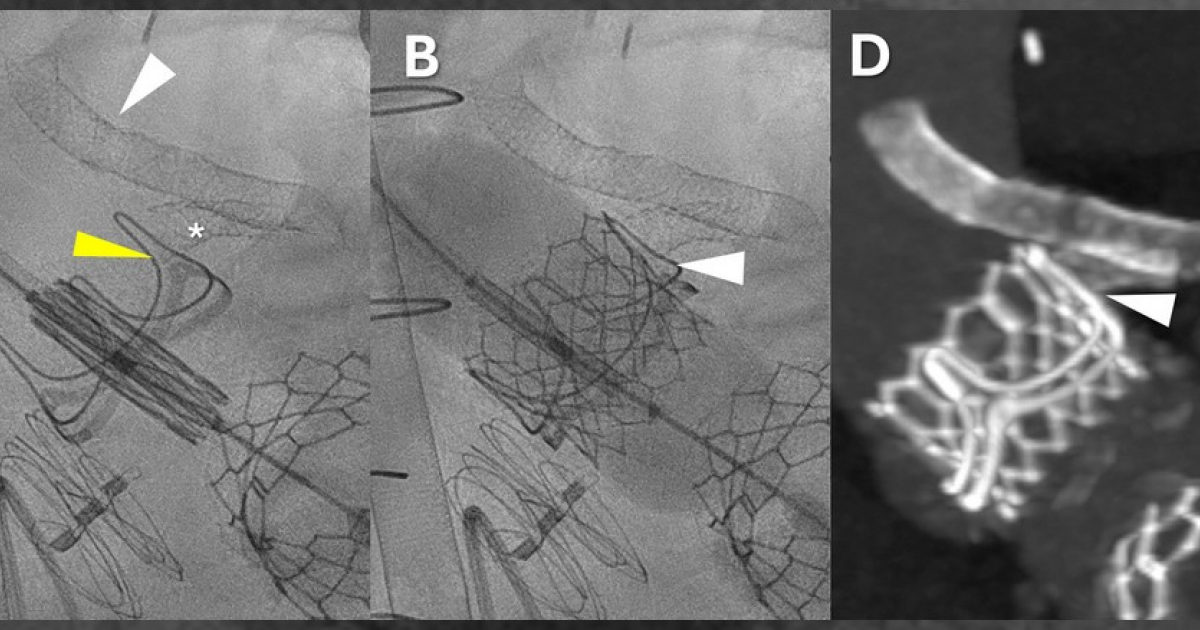

Американские врачи успешно провели первое в мире аортокоронарное шунтирование чрескожным доступом по бедренным сосудам без разрезов грудной клетки. Вмешательство провели пациенту в тяжелом общем состоянии, чтобы избежать перекрытия устья левой коронарной артерии при замене протеза аортального клапана, в которой он нуждался. Отчет об операции опубликован в журнале Circulation: Cardiovascular Interventions....